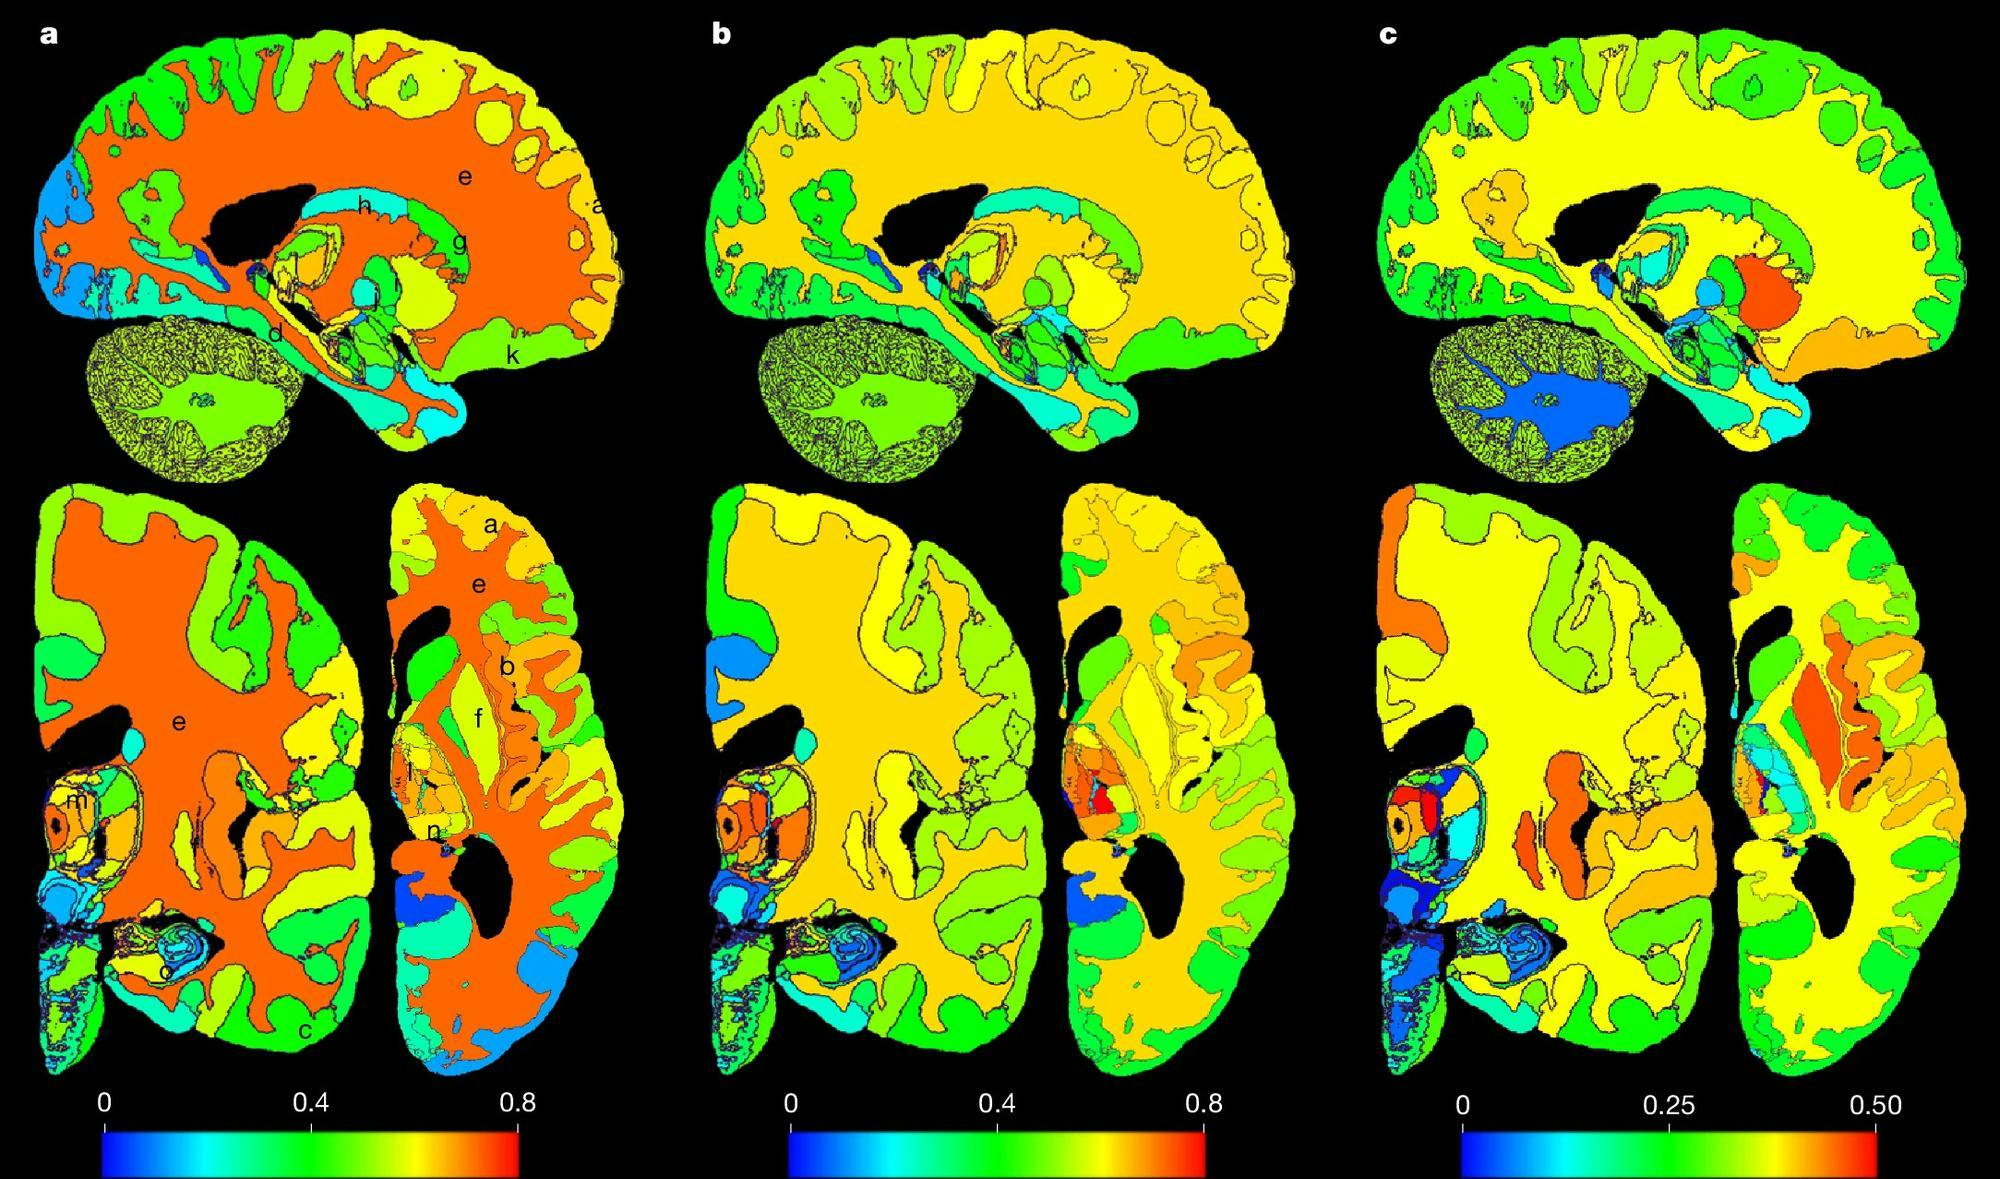

Recently, a neuroimaging study funded by the European Research Council introduced “NextBrain,” a three-dimensional, probabilistic, high-resolution brain atlas that maps the brain into 333 regions to assist with MRI analysis, powered by artificial intelligence. In neuroimaging, a brain atlas functions like a standardized coordinate system for the brain structure: It allows researchers and medical professionals to label and analyze the same anatomical regions across different brains so that results can be compared “in a common coordinate frame.”

Brain atlases can be used to analyze MRI scans of patients: While MRIs cannot capture high-resolution cellular information, brain atlases provide cellular data for comparison. Previous atlases relied primarily on either histology or MRI scans; NextBrain combined both to create a higher-resolution model. Histology involves dividing ex vivo (unalive) human brains into small pieces and staining them to reveal their cellular architecture. This process allows researchers to analyze tens of thousands of pieces in detail. On the other hand, MRI scans can be performed on living patients but lack the resolution to detect certain subregions crucial for early disease diagnosis or research. By connecting both approaches using Bayesian segmentation and machine-learning algorithms, researchers attained significantly higher accuracy. Earlier brain atlases typically mapped one or several brain regions without detailed labels. NextBrain changed this by identifying and labeling 333 “regions of interest” in the brain.

Following completion, researchers conducted “sanity check” experiments on Alzheimer's disease and aging patients. They applied the atlas to MRI scans from 168 Alzheimer’s patients and 215 healthy controls. The model achieved 90.3% accuracy, compared to 86.9% with the Allen MNI atlas, described as “the only competing histological (or rather, histology-inspired) atlas that can segment the whole brain in vivo.”